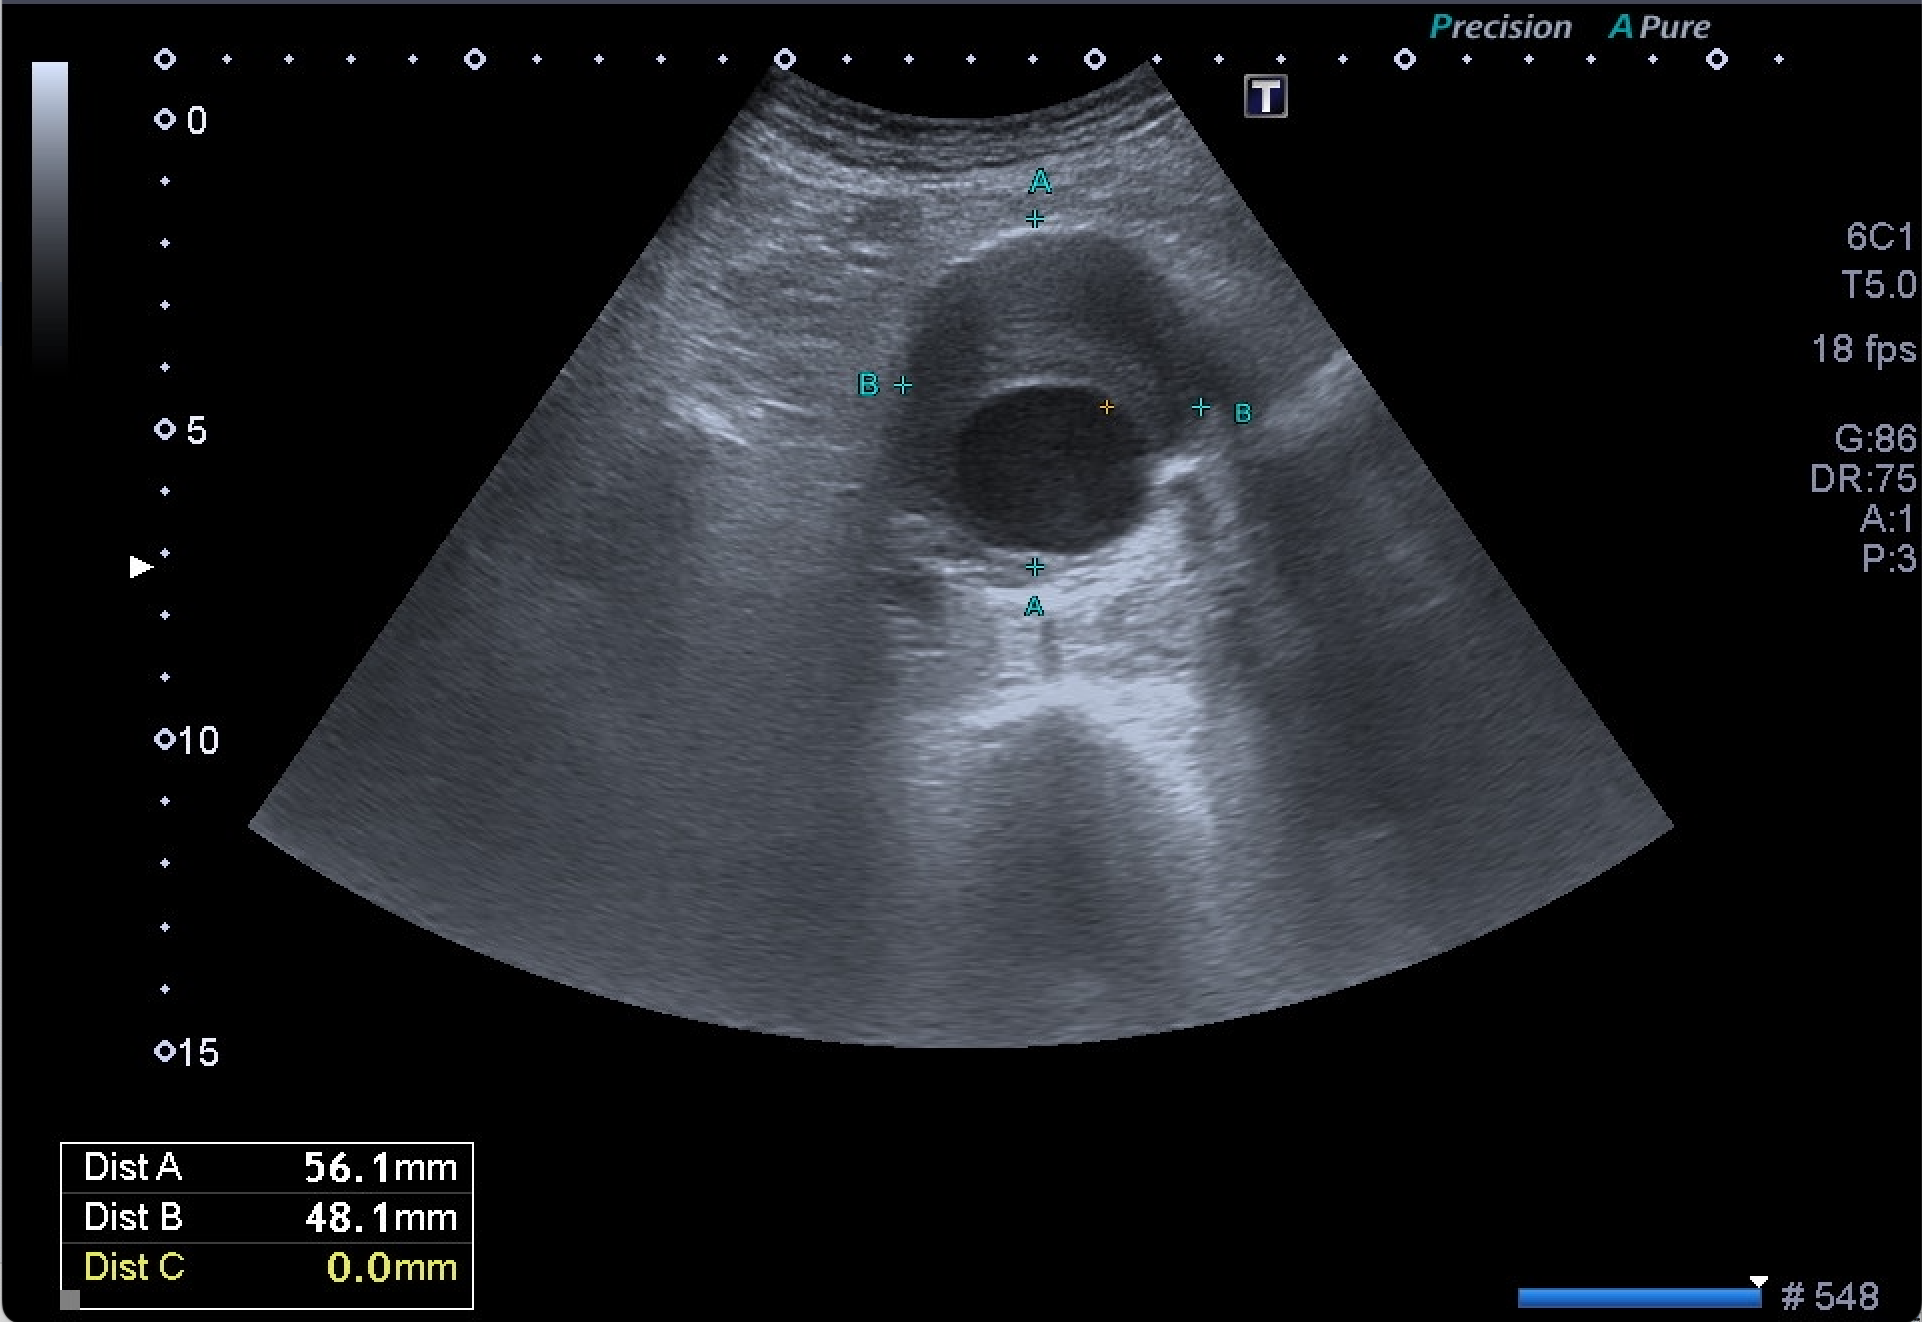

Destaca la visualización de probable litiasis renal derecha, junto con el hallazgo incidental de aneurisma de aorta abdominal, de unos 5,8 cm de diámetro máximo en el plano axial, el cual presenta trombo mural.